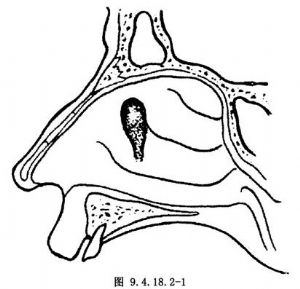

应用解剖:泪囊位于前后泪嵴间的泪囊窝内,长约12~15mm。前泪嵴由上颌骨额突构成,后泪嵴为泪骨的一部分。鼻泪管走行于上颌骨、泪骨和下鼻甲骨构成的骨性泪道内,长约18mm。泪囊定位是中鼻甲前端,鼻丘内侧,上界平中鼻甲附着处,前界为上颌骨额突,后界是钩突,下界是下鼻甲上缘,泪囊在鼻腔外侧壁的投影如图9.4.18.2-1。泪囊的骨性内壁由前部的上颌骨额突和后部的泪骨构成,中间有骨缝。